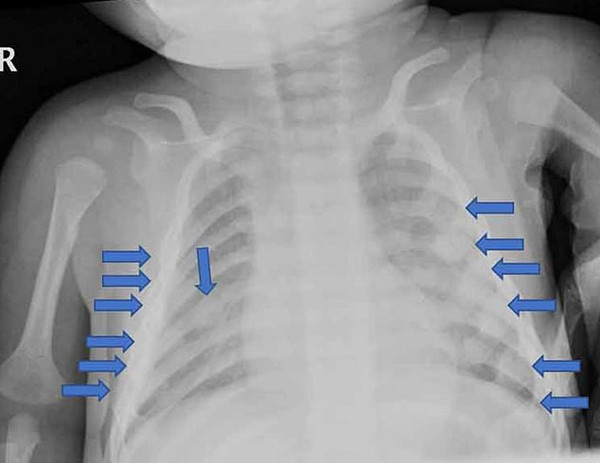

据报道,这起虐童事件于2017年2月曝光,当时这名男婴因手臂骨折被送往医院。这对夫妇向皇家萨塞克斯郡医院的医生谎报了男孩的痛苦以及他受重伤的原因,声称孩子被地毯凸起的一角绊倒了。后来医院发现男孩的伤势十分严重,肋骨骨折20处,膝盖、脚踝和都有骨折。儿科医学专家获取的证据显示,这些伤害是由强力所致,男孩骨折处是由于故意扭转、挤压造成的。医院确认骨折是在孩子被送到医院之前的四到六周之间造成的。